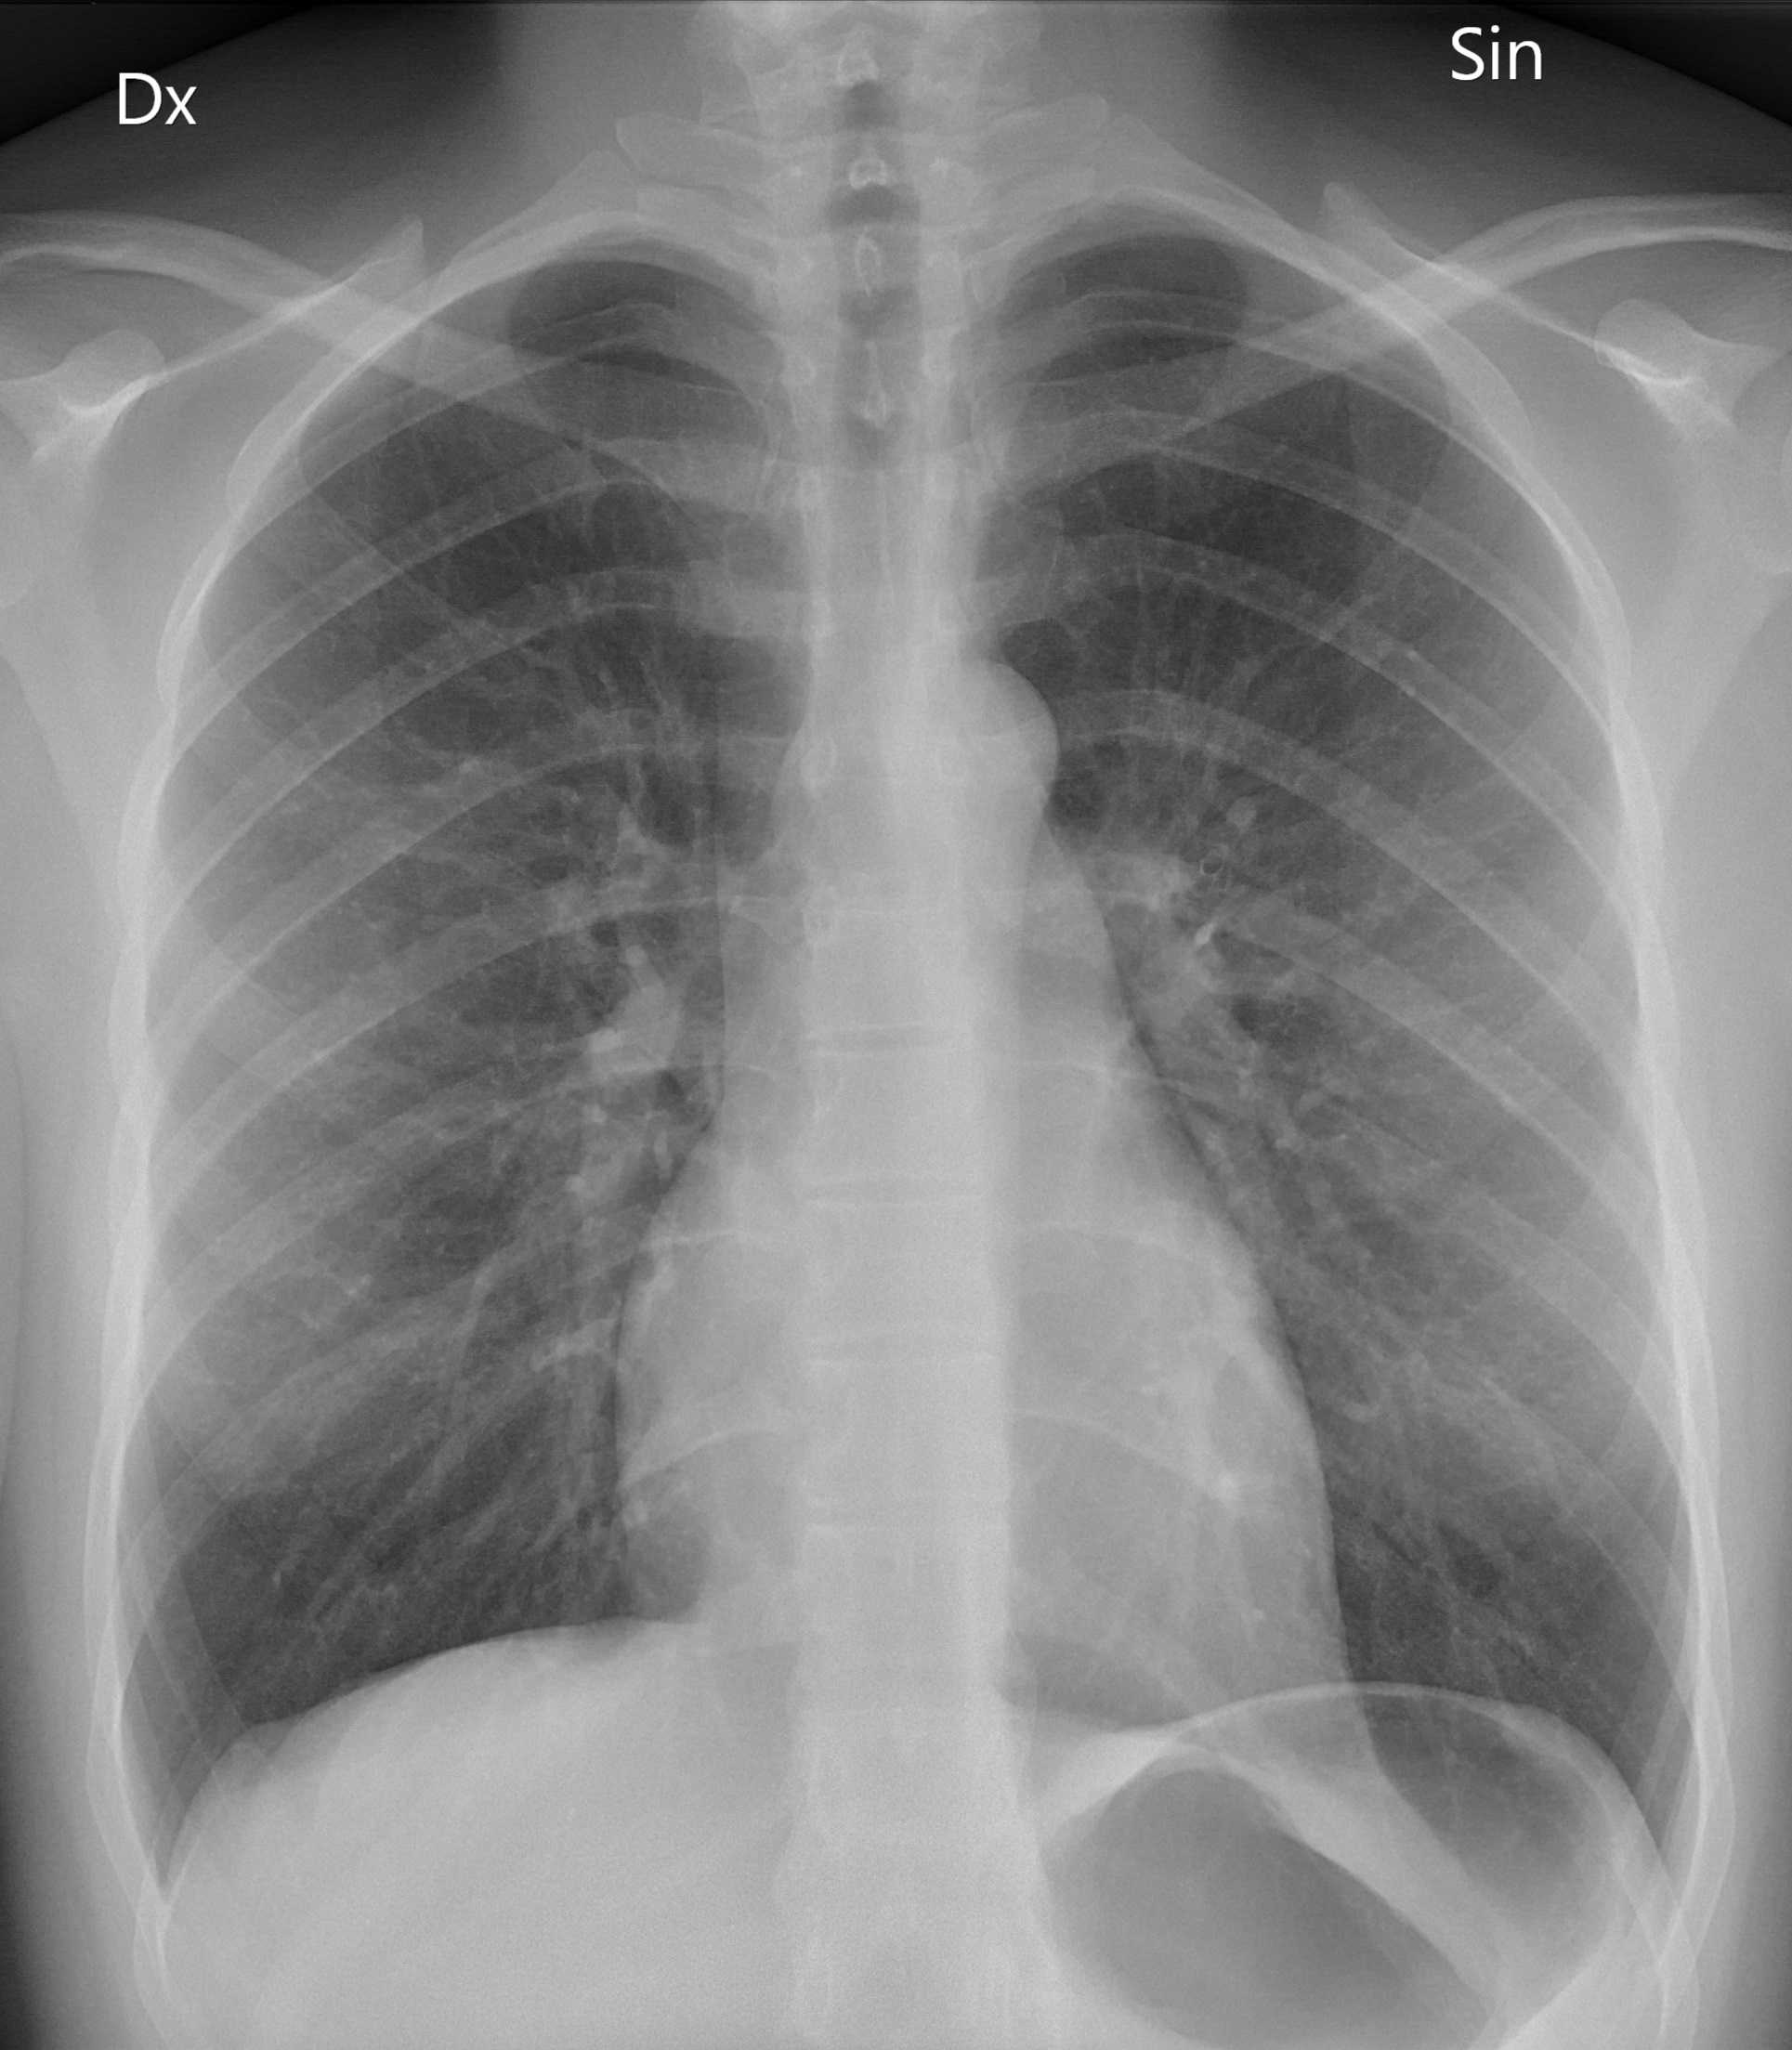

Chest X-Ray Analysis

SCAN-ID: 8492-MA-2024

Analysis complete. High reliability.

- Single-screen view of patient information, imaging, and AI analysis

- Real-time confidence scoring for AI recommendations

- Side-by-side original vs. AI-annotated image comparison

- Visual heatmaps showing AI focus areas on medical images